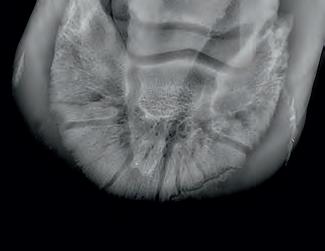

Diagnosis of ulcers in the stomach using a Gastroscope.

Radiographic proof in clinical results

BONE Gold nutritional bone joint and collagen supplement was formulated to provide some of the essential amino acid requirements of collagen type I, II and III (found in bone and connective tissue) in addition to supporting the nitric oxide pathway which has been found to assist in the formation of bone callus postinjury.

Veterinary surgeons have recommended that Bone Gold may assist with sore shins, tendon injuries, ligament injuries, osteoarthritis and post-surgery in horses and polyarthritis, geriatric osteoarthritis, and post-surgery in dogs.

Here is a veterinary radiographic report on a horse with a fracture evident on the medial toe and after treatment and feeding Bone Gold during this period. More information on these products can be found at www.vetgold.com.au

VETERINARY RADIOGRAPHIC REPORT

HORSE: "XXXXXXXX"

DATES OF EXAMINATION: 26TH AUG, 21ST OCT 21 & 17TH NOV '21

PLACE: XXXXXXXXXX FARM

XXXXXXX's left and right front feet were radiographed on 26th Aug, 21st Oct (8 weeks) and again on the 17th Nov '21(12 weeks).

RADIOGRAPHS:

26.08.21: Right Front: Large P3 solar margin fracture evident on medial toe 32.6mm x 4.1mm with approximately 1.4mm separation from parent bone as below left image.

21.10.21: Right Front: Fine residual 4.2mm fracture still evident, approximately 90% resolution

17.11.21: Right Front: Fracture fully resolved

RECOMMENDATIONS:

Radiographic results as of the 17th Nov '21 show total resolution of the original fracture.

XXXXXXX was reshod today utilising off an alloy shoe with a toe clip - inner circumference seated out to avoid any sole pressure.

The horse can return to training. Please do not hesitate to contact me if you have any further queries

COMMENTS:

Solar margin Type IV fractures of this magnitude have well-documented internationally published healing rates of 7 - 12 months. Full resolution of these fractures is rare as most often the fracture fragments are resorbed.

Full resolution in a 3 month period was not anticipated.

The horse was on Bone Gold 3 x scoops fed once per day for this period.

"Go to our webpage or scan the QR Code to see more Bone Gold Radiographic results"